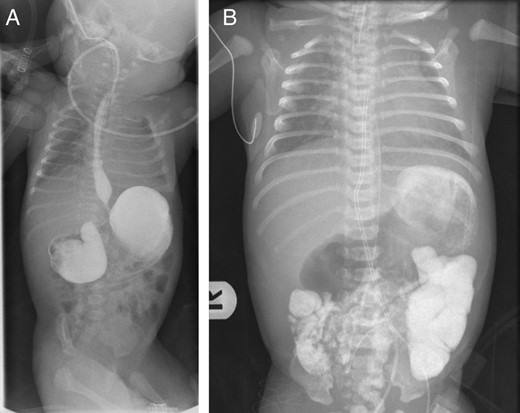

A 2-day-old girl was referred to our service with sudden onset of severe hematemesis. Prenatal history was significant for intrauterine growth retardation. She was born at the gestational age of 37/40 with a birth weight of 2.1 kg. On examination she was found to have dysmorphic features suggestive of Down's syndrome, along with hypotonia, intercostal muscle retraction and a mildly distended epigastric region. She was suspected of meconium aspiration and sepsis. Her initial investigations revealed WBC of 20 100 μl, Hb of 16.8 g/dl, platelets of 114 000/μl and CRP of 10 md/l. After intravenous antibiotics, she remained stable but on Day 2 of life, she was noted to have high levels of orogastric aspirates mixed with blood. A plain X-ray revealed a dilated stomach and duodenum, with air in the distal small bowel (Fig. 1). An APT test was negative. Repeat laboratory evaluation revealed WBC of 23 200 μl, Hb of 10.1 g/dl and platelets of 140 000/μl. She was started on ranitidine 10 mg daily but she continued to have fresh blood in her orogastric tube and her hemoglobin level dropped to 8.0 g/dl with INR 10, PT 120′ and APTT 180′. She was managed accordingly and after resuscitation, an upper GI contrast study was performed to rule out malrotation or mid-gut volvulus. Her upper GI contrast suggested an incomplete duodenal obstruction (Fig. 2). To look for a source of bleeding, an upper GI endoscopy was not performed due to duodenal obstruction and a risk of perforation. The baby was taken to the operating theater for exploration to determine the cause of her ongoing hematemesis and to correct her duodenal obstruction. On exploration, her stomach and proximal duodenum were dilated with a narrowing noted in the second part of the duodenum. There was no malrotation of her gut and the rest of the bowel and solid viscera were normal. A duodenotomy of her proximal dilated duodenum revealed a complete diaphragm with a hole allowing passage of a small probe down into the distal duodenum. The mucosa of the proximal dilated duodenum was edematous and friable with multiple erosions. She underwent diamond-shaped duodenoduodenostomy for her CIDO. Her postoperative course was uneventful and hematemesis resolved. She was started on gradual nasogastric to oral feeding, which she tolerated very well. Further investigations revealed a right ectopic kidney and minor congenital cardiac defects. Her chromosomal analysis showed a karyotype of 47, XX, + 21 consistent with Down's syndrome.

(A) Upper gastrointestinal contrast study showing a markedly distended stomach and duodenal bulb, with narrowed second part of duodenum suggesting congenital duodenal obstruction. (B) Delayed film of upper gastrointestinal contrast study showing dye passing distally suggestive of incomplete obstruction